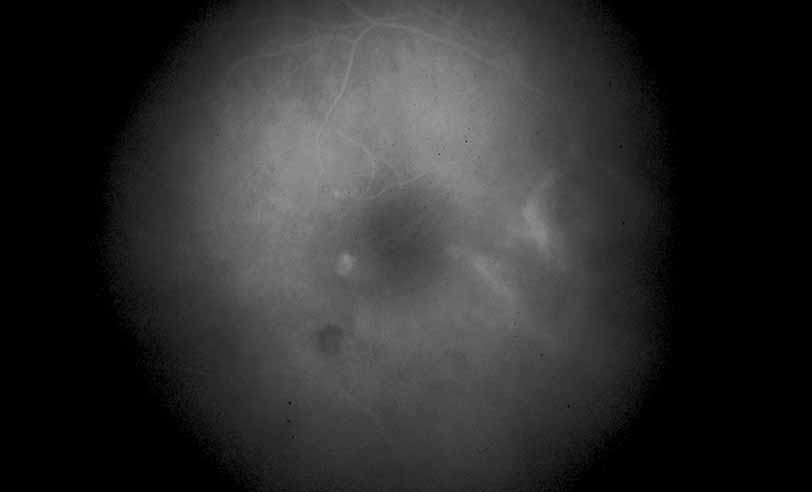

Fig. 28 Serpiginous choroiditis. ICG angiography early frame shows multiple hypofluorescent spots in the location of the lesions seen on color photography.

Fig. 29 Serpiginous choroiditis. ICG angiography later frame shows multiple hypofluorescent spots in the location of the lesions seen on color photography.